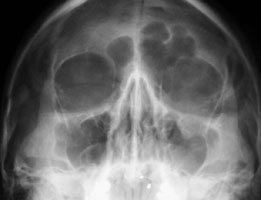

Blowout fractures are caused by direct trauma to the globe which causes an increase in intraorbital pressure and decompression via fracture of the orbital floor. Radiographically, fragments may be seen in the maxillary sinus or there may be opacification of the maxillary sinus with blood. Clinically, there may be diplopia on upward gaze due to entrapment of the inferior rectus muscle.

- Click on the image for a larger versionAWaters' radiograph. This reveals herniation of fat into the left maxillary sinus, due to an orbital floor fracture.